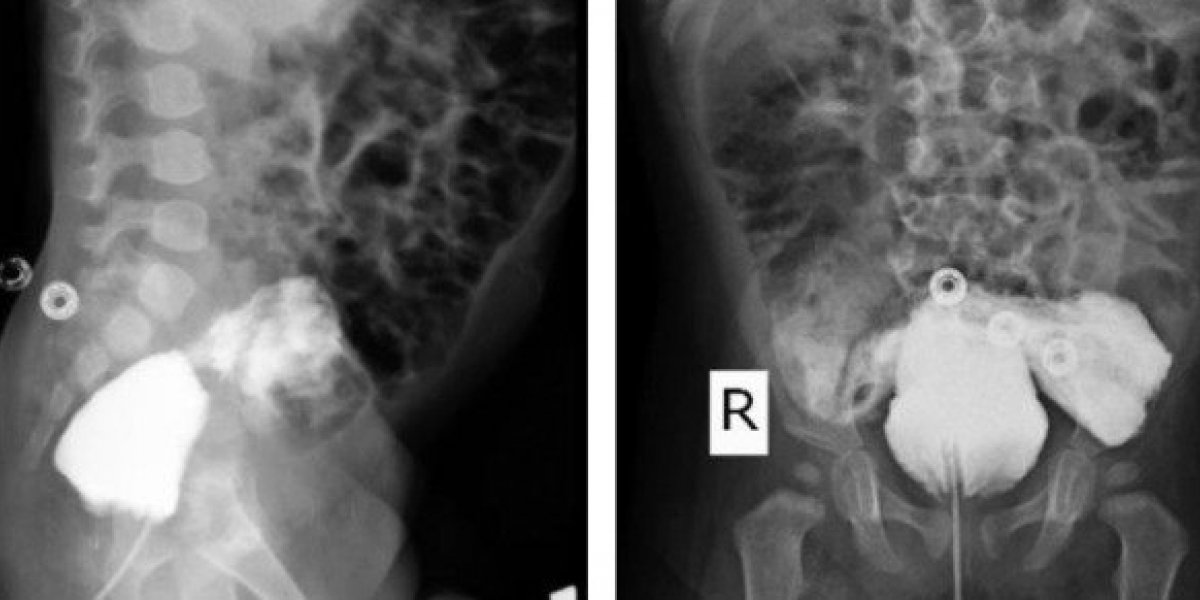

A equipe realizou exames por mais de um ano após o nascimento da criança para entender como funciona o sistema urinário único do paciente. Em exames de imagem com um corante específico, foi identificado que o bebê tem uma fístula, ou seja, uma ligação anormal entre a bexiga e o reto – que fica no final do intestino.